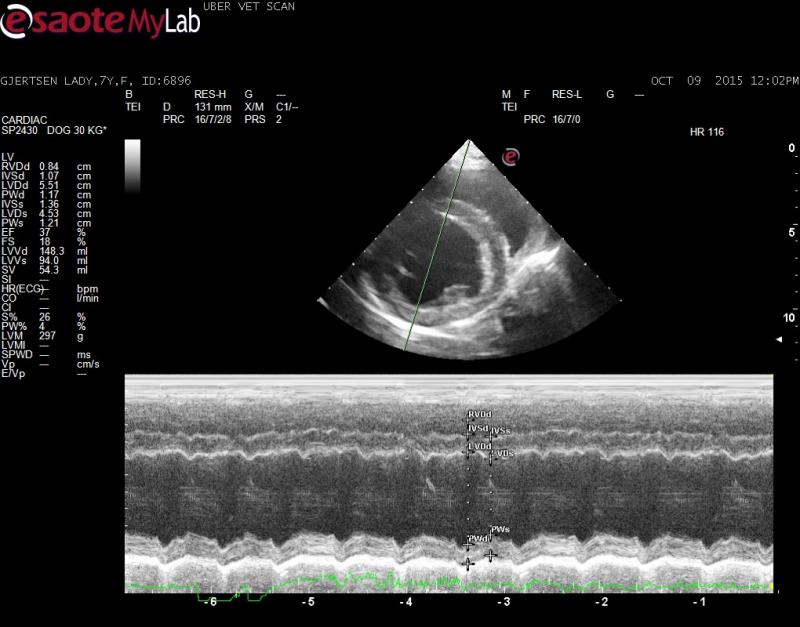

– echo showed normal LV parameters (no eccentic hypertrophy documented) however EPSS is elevated and FS% decreased

Innapropriate wall thickening

Innapropriate wall thickening with dilated L ventricular chamber elevated EPSS and poor FS to me indicates cardiomyopathy. Consider a mitral inflow study to get some sort of idea of L atrial pressure. I am suprised the L atrium is not more dilated.

The mitral inflows were wnl and the LV chamber and walls were also wnl when using the Cornell reference ranges and the GD breed specific tables but the FS% and EPSS sure points toward occult DCM to me.